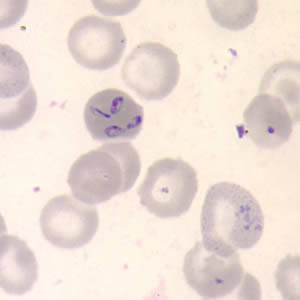

Babesia